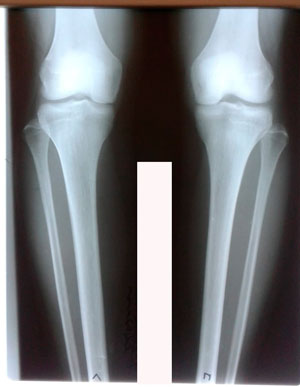

Исходник - 28 лет.

Дата операции - 04.06.2020

До круток

Ножки на сегодня